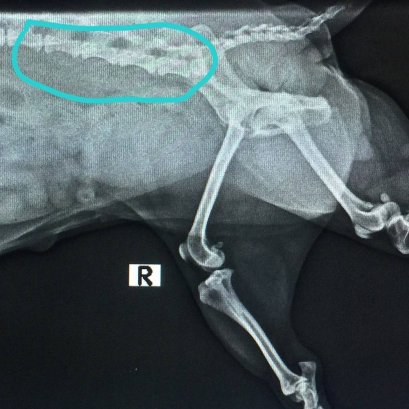

น้องสุนัขเด็กมาด้วยอาการเบ่งถ่ายเป็นเลือดสด มีกลิ่นคาว ปวดเบ่ง คุณหมอจำคลำท้องพบว่าแข็ง ปวดท้องมาก และอ่อนเพลียจากการเสียเลือดมาก ซักประวัติเจ้าของให้กินโครงไก่สับเป็นอาหาร จึงต้องนำน้องไป x-ray และตรวจเลือด ภาพ x-ray พบกระดูกชิ้นเล็กๆ จำนวนมากอัดแพ็คตัวแน่นอยู่ที่ลำไส้ใหญ่ ค่าเม็ดเลือดแดงและเกล็ดต่ำ บ่งบอกถึงการมีเลือดออกจนสูญเสียเม็ดเลือดแดงและเกล็ดเลือดไปมาก